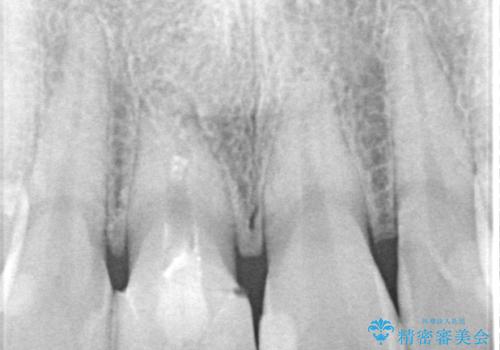

- 数年前に他院で治療した右上の前歯の色が不自然なことを主訴として来院された患者様です。

隣在歯と色、形ともに合っていません。

また、被せものと土台の境目が歯肉よりも上に見えていて、段差になっています。

そのため審美性、清掃性どちらの観点からもあまりよくない状態です。

不適合な被せものを除去し、土台の歯の形を修正し、精度の高いシリコーンによる型どりをしました。